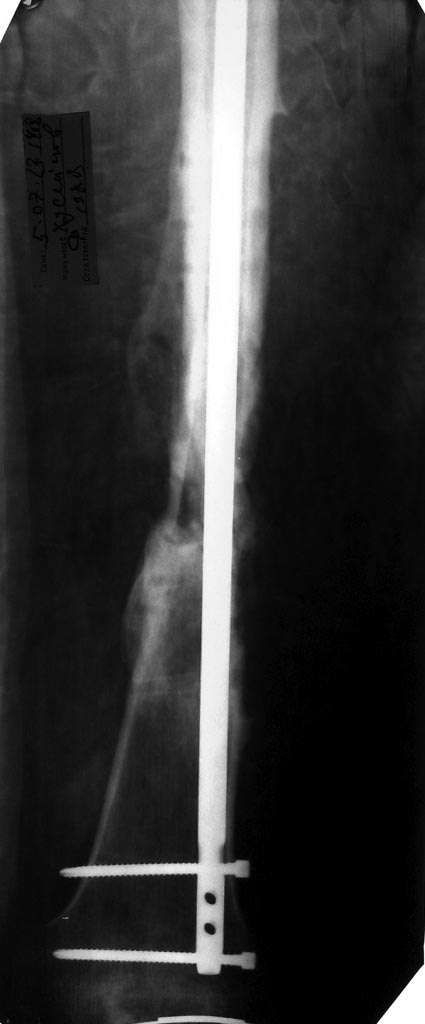

Уважаемые коллеги! Помогите определиться с тактикой лечения у молодого

пациента.

Молодой парень, 25лет. Травму получил в ноябре 2012 года, ДТП.Оперирован

в сельской больнице, остеосинтез перелома бедренной кости пластиной и

АВФ на голень с этой стороны, наложена гипсовая повязка коксит на 3

месяца. В момент госпитализации разгибательная контрактура коленного

сустава (движения в коленном суставе сгибание 10 градусов) 02.07.2013

произведена операция - удаление металоконструкции с бедренной кости,

костная аутопластика( из подвздошной кости) и БИОС бедренной кости

универсальным гвоздем ChM. ЭОПа у нас нет, пользуемся переносным

рентгенапаратом. Как быть с ложным суставом голени?

1. БИОС голени- оптимальный вариант,но при отсутствии желаемого сгибания

в коленном суставе сможем ли мы сделать( Наш опыт - всего 30 операций по

БИОСу)

2ЧКДО по Илизарову( после АВФ)